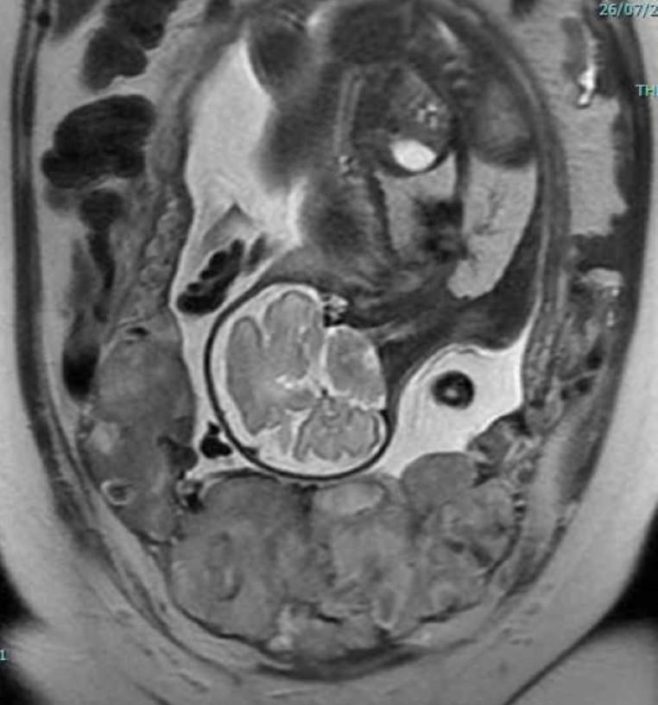

In some cases, magnetic resonance imaging (MRI) may be used to help assess the severity of the condition and how far the placenta has spread before planning treatment.